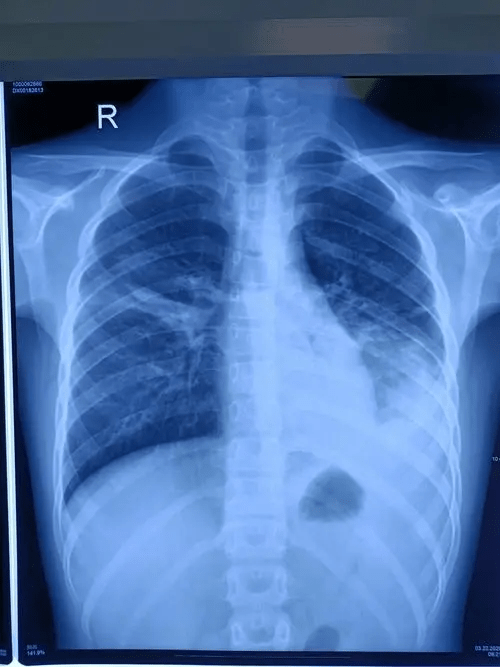

▲有患者染病后肺部变白。